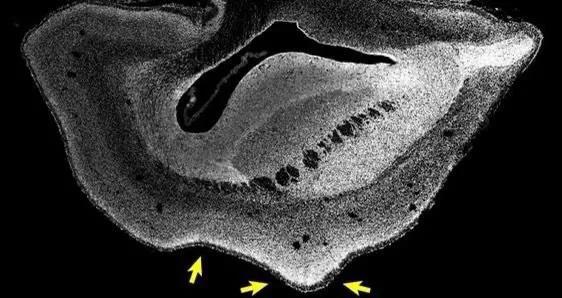

這個基因的表達有利於腦幹細胞的發育,讓大腦發育過程中產生更更多的神經元,科學家用非常簡單的辦法就驗證了他們的結論。他們把這個基因轉移到絨猴的胚胎中讓它們表達,最後發現實驗對象絨猴大腦裡出現了新的皮質區域,並且增加了大腦皮層上的皺褶,呈現出腦回樣結構。